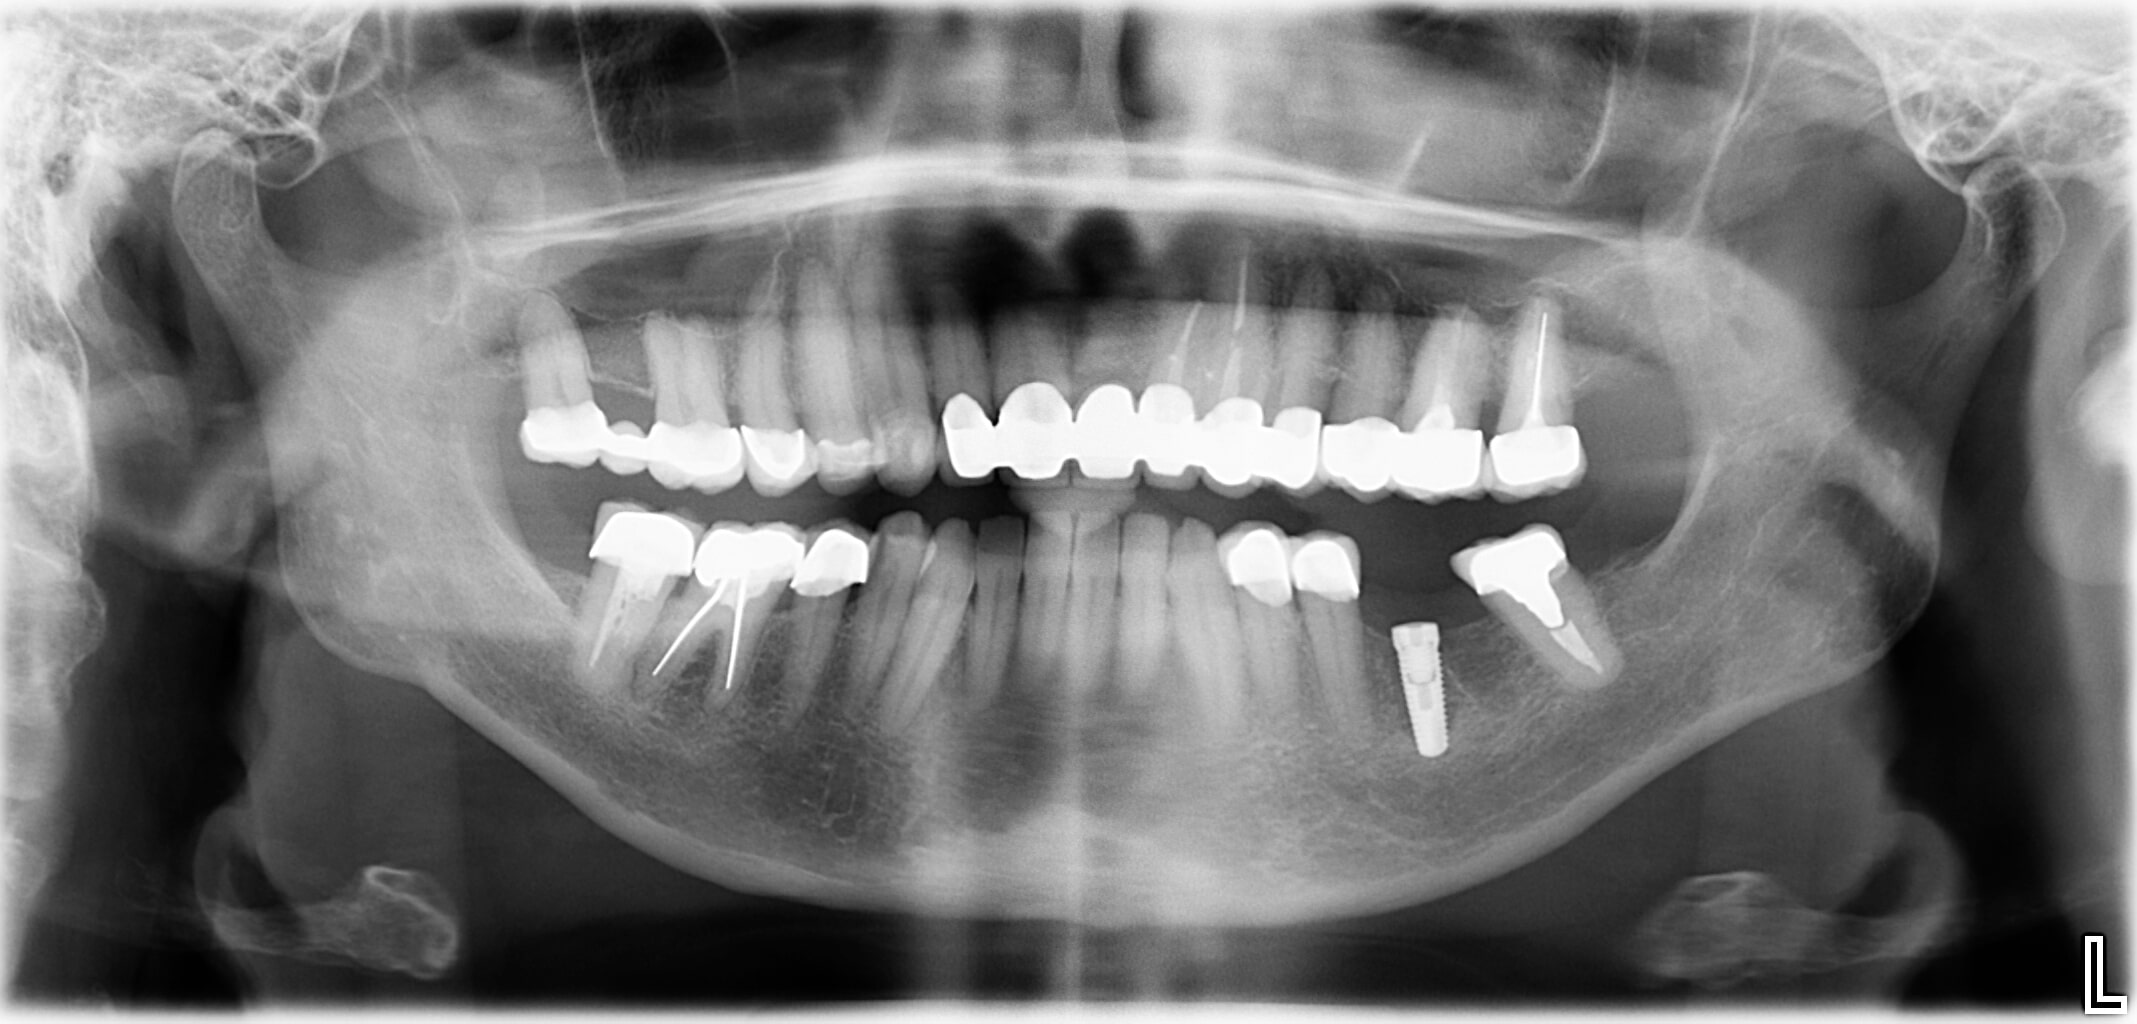

Und Sie denken dabei an eine nachhaltige Lösung mit einem Implantat? Dann machen Sie den ersten Schritt und vereinbaren Sie einen Beratungstermin in unserer Zahnarztpraxis Dr. Kaiser in Draßburg im Burgenland. Zahnimplantate ermöglichen einen dauerhaften Zahnersatz, der noch dazu sehr natürlich aussieht. Wir beraten Sie gerne und sorgen dafür, dass Sie Ihre schönen Zähne bei jedem Bissen und jedem Lächeln voll und ganz genießen können.

Unsere Zähne übernehmen nicht nur die Nahrungszerkleinerung, sie sind auch ausschlaggebend für unsere Aussprache und prägen vor allem unser Aussehen. Wer einen Zahn verliert, sei es durch einen Unfall oder als Folge einer Erkrankung, wünscht sich einen schönen und haltbaren Zahnersatz. Mit Zahnimplantaten können wir diese Wünsche vollends erfüllen.